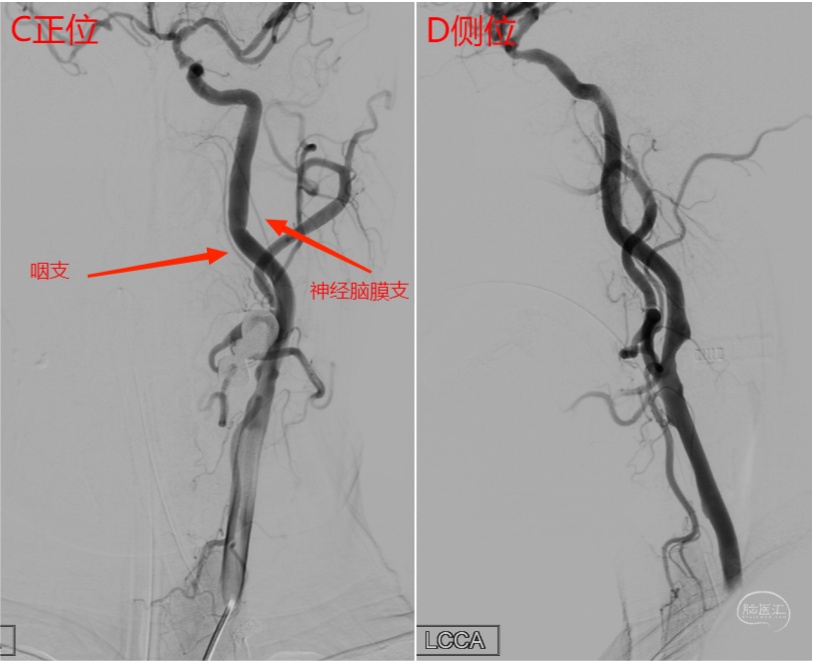

图13 左侧颈总动脉正位(C)及侧位(D)造影。由于颈内动脉遮挡,咽升动脉在侧位显示不清。正位可见咽升动脉咽支自颈内动脉发出,神经脑膜支在枕动脉发出(详见下图3D及Xper CT)。

图14 左侧颈总动脉3D(E)及Xper CT重建(F)图像。可见咽升动脉咽支自颈内动脉发出,供血至咽部。